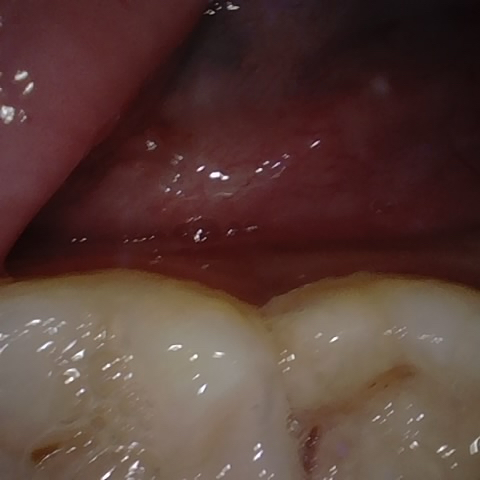

Annotated as "Good"